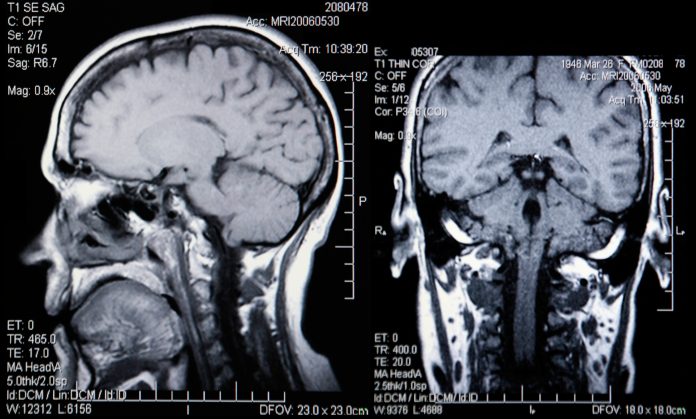

Epilepsy Research UK Emerging Leader Fellow and trainee neurosurgeon Mr Ashan Jayasekera has pioneered a new surgical method used to treat seizures in patients with brain tumours. Based at Newcastle University, Ashan’s research developed a non-invasive technique using MRI scans to pinpoint which parts of the brain tissue need to be removed to halt seizures, while causing minimal disruption to the rest of the brain.

However, removing the tumour may not necessarily prevent seizures as they do not start in the tumour – they originate in the part of the brain next to the tumour. Ashan explains, “This poses a problem to the surgeon: which bits of the surrounding brain should they remove to render a patient seizure-free? How much do they need to remove? Traditionally surgeons have worked in conjunction with neurophysiologists to map the areas of seizure generating brain, by placing grids of electrodes around tumours and looking for any abnormal electrical activity. However, doing this involves another operation that carries risks and it’s not yet clear how effective this method is.”

“This is where my research – very generously funded by an Epilepsy Research UK Emerging Leader Fellowship Award – comes in. I wanted to demonstrate that areas of the brain around a tumour with high levels of glutamate could be responsible for generating seizures. As part of the research, patients would have MR spectroscopy scans prior to their surgery, and a sample of tissue would be taken to the lab to look for any spontaneous seizure activity.”

Through this project, Ashan discovered that tissue that had been connected to spontaneous seizures came from areas of the brain around a tumour with high glutamate levels. This is the first time this has been demonstrated in the lab and is an important step towards showing that MR spectroscopy could be used in mapping the areas of the brain responsible for seizures in patients with gliomas.